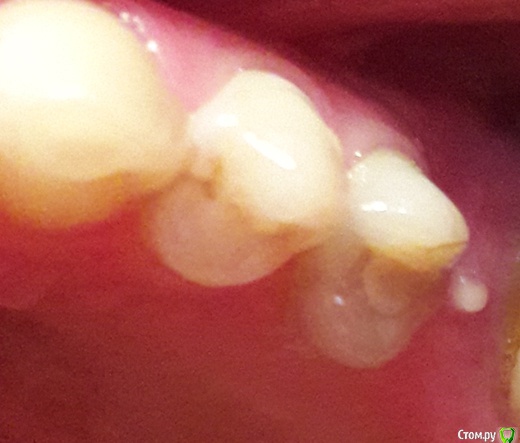

венди Опубликовано 27 февраля, 2017 Автор Поделиться Опубликовано 27 февраля, 2017 (изменено) Добрый день! Наверное, мой вопрос сейчас больше для раздела Хирургии. Но не знаю создавать ли новую тему, поэтому пишу здесь. Если нужно - перенесу. Напомню, что перед Новым годом был выкручен ФДМ, т.к. не проходило какое-то воспаление и очень сильный дискомфорт. Десна после выкручивания постепенно затянулась. Оставалось малюсенькое отверстие - через него хирург засовывал что-то острое и проверял имплант месяц назад, когда я ходила на осмотр. Пару дней назад появилась болезненность, когда кушала на левую сторону именно в области десны, где имплант. А на выходных образовался какой-то прыщик. Фото прилагаю.Сегодня ватной палочкой, смоченной в хлоргексидине его потрогала - выделилась капелька жёлтого цвета и он сильно сдулся. Что это может быть? Слизистая так выросла? Изменено 27 февраля, 2017 пользователем венди Ссылка на комментарий